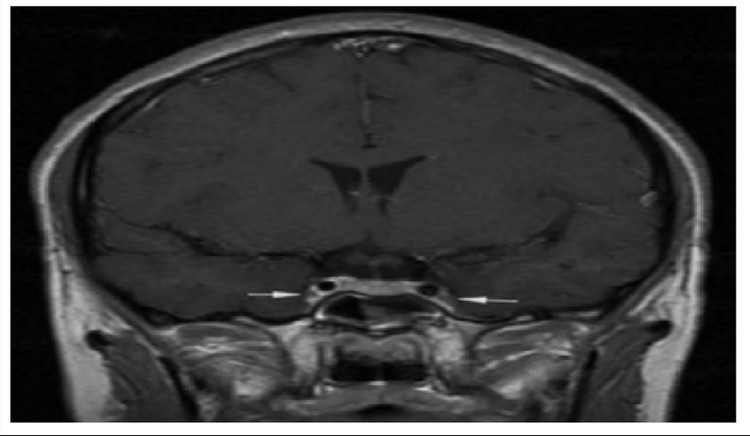

Theo hồ sơ bệnh án, bệnh nhân khởi phát bằng viêm xoang cấp mủ, sau đó chuyển sang viêm tấy nửa mặt, rồi nhanh chóng xuất hiện rối loạn ý thức và co giật. Kết quả chụp cộng hưởng từ sọ não cho thấy: Phù nề lan tỏa, dấu hiệu điển hình của viêm tắc tĩnh mạch xoang hang - một tình trạng huyết khối nhiễm trùng ở nền sọ.

xoang-hang-1.jpg

Xoang hang - Ảnh BVCC

Bác sĩ Nguyễn Hữu Hồng Quân - Trung tâm Cấp cứu A9, Bệnh viện Bạch Mai cho biết: “Xoang hang là vùng tĩnh mạch nằm sâu trong nền sọ, chứa dây thần kinh và động mạch cảnh đi vào.